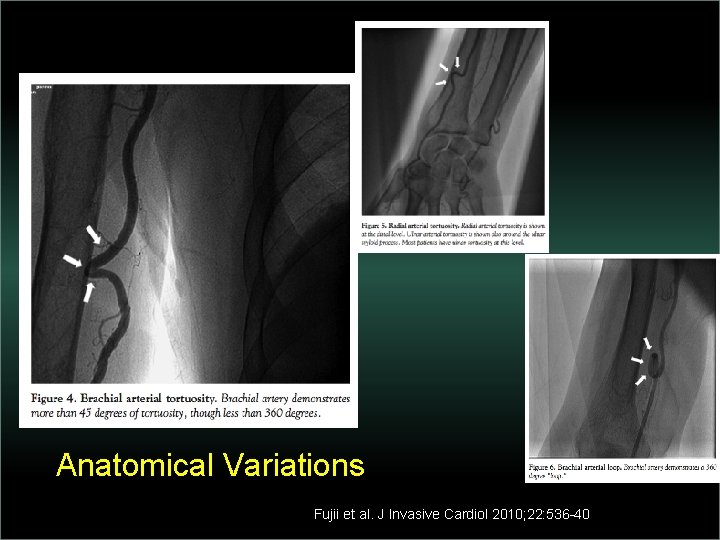

Transradial Interventions Difficult Anatomic Substrate Challenges and Solutions